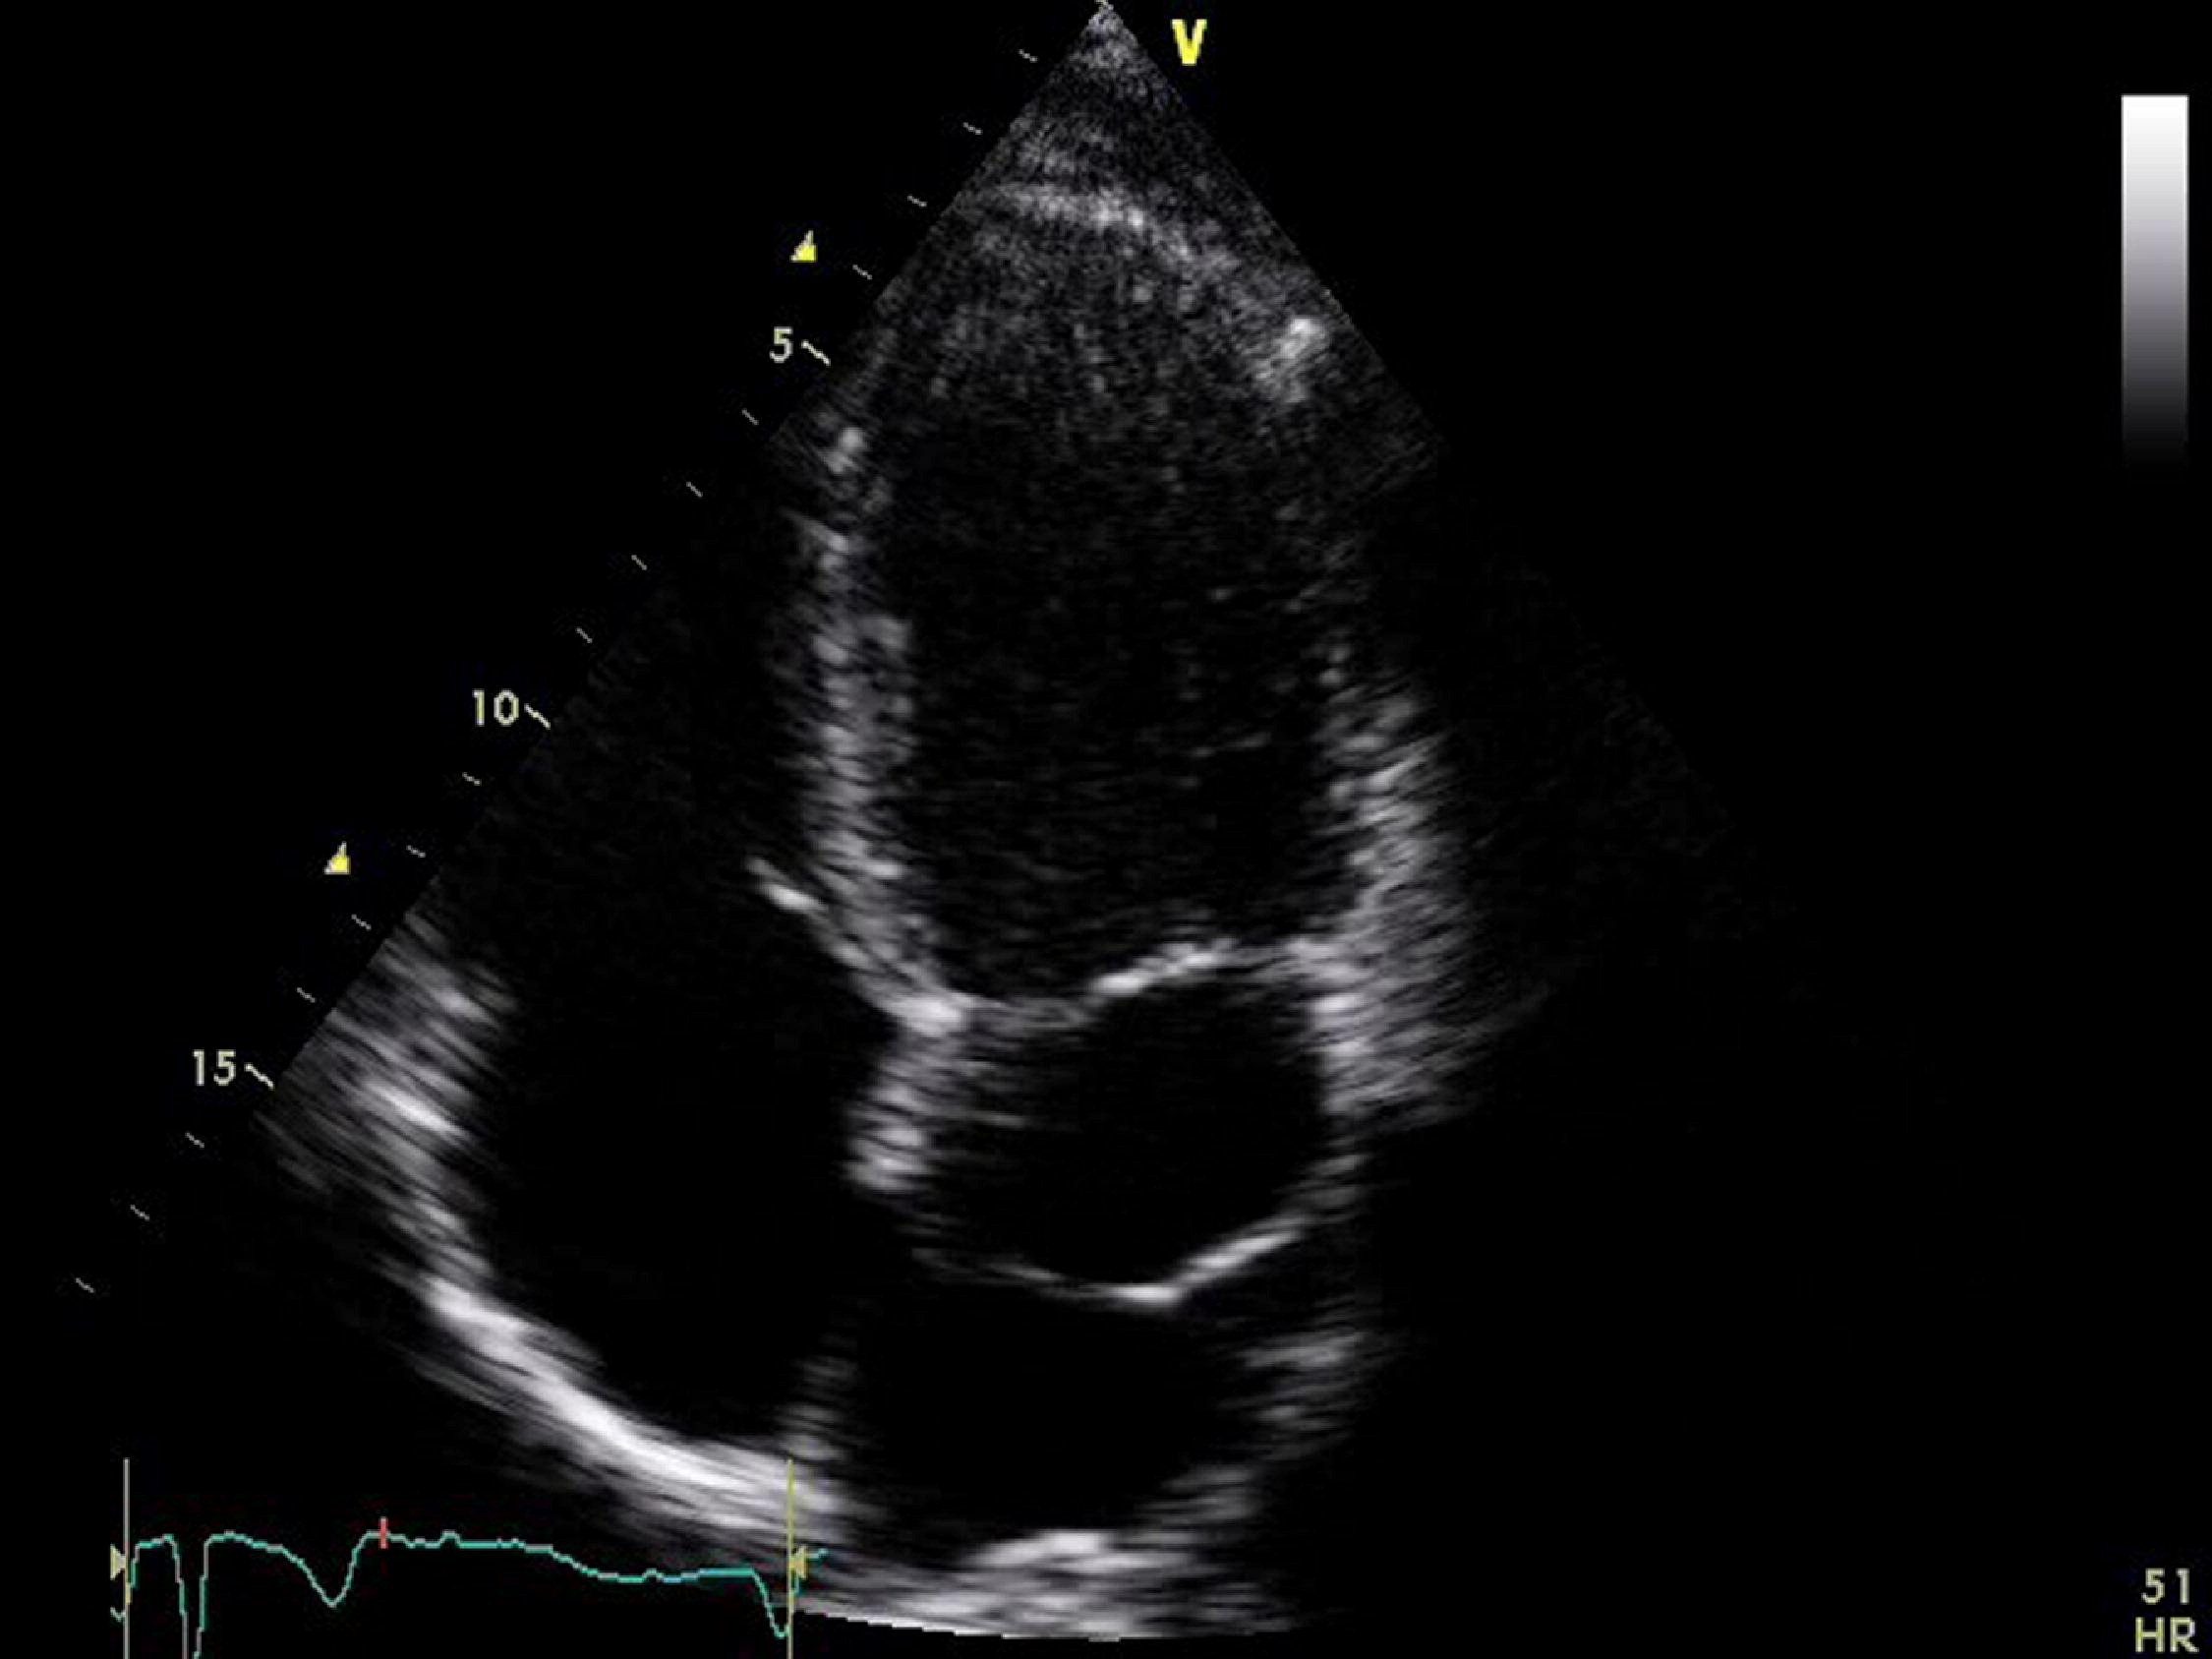

What is seen in the 2D image?

True cardiac aneurysm